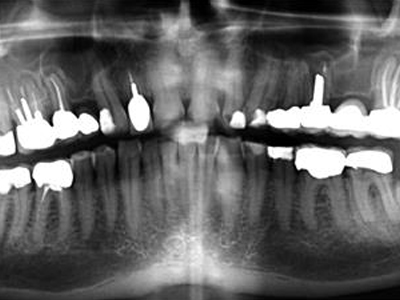

RCT is performed for apical periodontitis to remove infected tissue from the root canal, facilitate periapical tissue repair, and prevent further infection. The goal is a non-surgical, tooth-saving therapy to eliminate bacteria and seal the root canal system. While success rates for primary RCT are high (68-85%), healing can take months to years, and a successful coronal restoration is critical for long-term tooth survival.

Clinical & Radiographic Monitoring :

Healing is assessed by clinical signs and radiographic changes in the periapical tissue over time, with complete healing sometimes taking several years